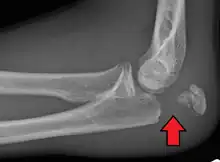

To assess an olecranon fracture, a careful skin exam is performed to ensure there is no open fracture. Then a complete neurological exam of the upper limb should be documented.[5][2] Frontal and lateral X-ray views of the elbow are typically done to investigate the possibility of an olecranon fracture.[1] A true lateral x-ray is essential to determine the fracture pattern, degree of displacement, comminution, and the degree of articular involvement.

Most olecranon fractures are displaced and are best treated surgically:[1]

Tension band fixation is the most common form of internal fixation used for non-comminuted olecranon fractures.[5] It is typically reserved for noncomminuted fractures that are proximal to the coronoid.[2] This procedure is performed using Kirschner wire (K-wires) which converts tensile forces into compressive force.[2]